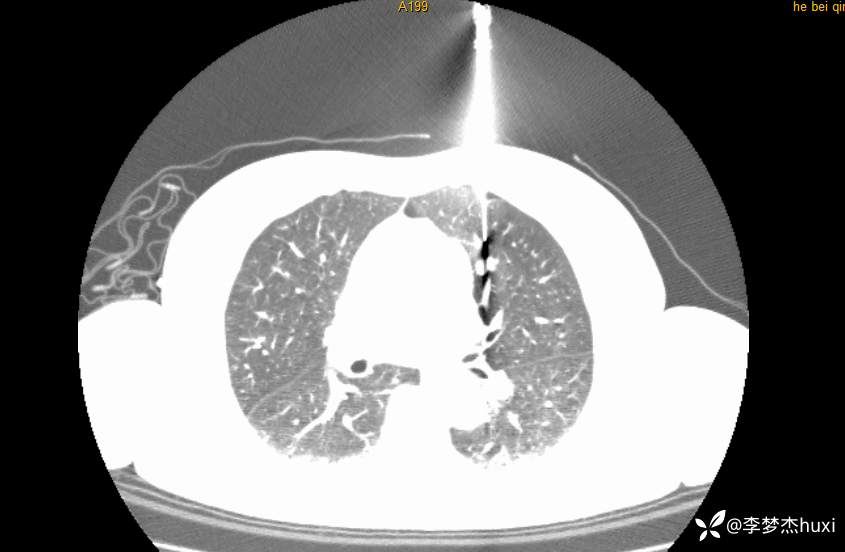

1.现病史:患者老年 女,患者于入院前3天(2024-06-02)体检查胸部CT:左肺部分实性结节,右肺磨玻璃结节,左肺上叶实性结节--性质?建议肺结节门诊会诊检查;双肺索条,双肺下叶条絮状高密度影--考虑肺血坠积效应,主动脉壁钙化,双侧胸膜局部增厚,左侧乳腺钙化点。2024-06-04查胸部增强CT:左肺上叶实性结节--占位?建议结合病理;左肺部分实性结节,右肺磨玻璃结节,建议肺结节门诊会诊检查;双肺索条,主动脉壁钙化,双侧胸膜局部增厚,左侧乳腺钙化点。患者目前无咳嗽、咳痰,无发热,无胸痛,今为求进一步诊治来我院,门诊以“肺诊断性影像异常”收入院。

4.辅助检查:2024-06-02查胸部CT:左肺部分实性结节,右肺磨玻璃结节,左肺上叶实性结节--性质?建议肺结节门诊会诊检查;双肺索条,双肺下叶条絮状高密度影--考虑肺血坠积效应,主动脉壁钙化,双侧胸膜局部增厚,左侧乳腺钙化点。2024-06-04查胸部增强CT:左肺上叶实性结节--占位?建议结合病理;左肺部分实性结节,右肺磨玻璃结节,建议肺结节门诊会诊检查;双肺索条,主动脉壁钙化,双侧胸膜局部增厚,左侧乳腺钙化点。。